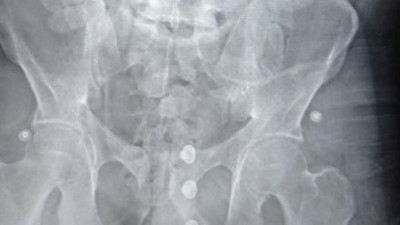

Ne bulduysa mideye indirmiş. Mide değil sanki hurdalık Van'da karın ağrısı şikâyetiyle hastaneye başvuran 35 yaşındaki gencin midesinden 1 liralık 83 madeni para, pil, mıknatıs, çivi, cam parçaları, taş ve vida gibi 233 cisim çıkarıldı.